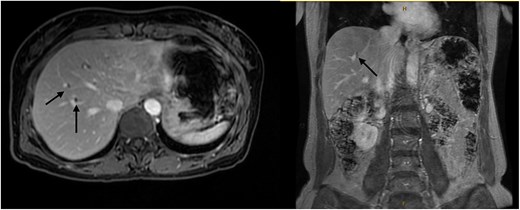

Six months after surveillance imaging, she was presented with ongoing abdominal pain. Liver function tests (LFTs) and Ca 19–9 remained normal at this time. A repeat abdominal US demonstrated an irregular gallbladder wall with thickening up to 5 mm and two stable gallbladder polyps, the largest measuring 7 × 8 mm (Fig. 2). Due to ongoing symptoms and changes on imaging, a laparoscopic cholecystectomy with intraoperative cholangiogram was performed without complication. At the time of surgery, the gallbladder was noted to have an area of wall thickening thought to be a Phrygian cap. The operative cholangiogram was consistent with PSC, with narrowed intrahepatic ducts observed (Fig. 3).

Intraoperative cholangiogram demonstrating intrahepatic duct stricturing (arrows) consistent with PSC.